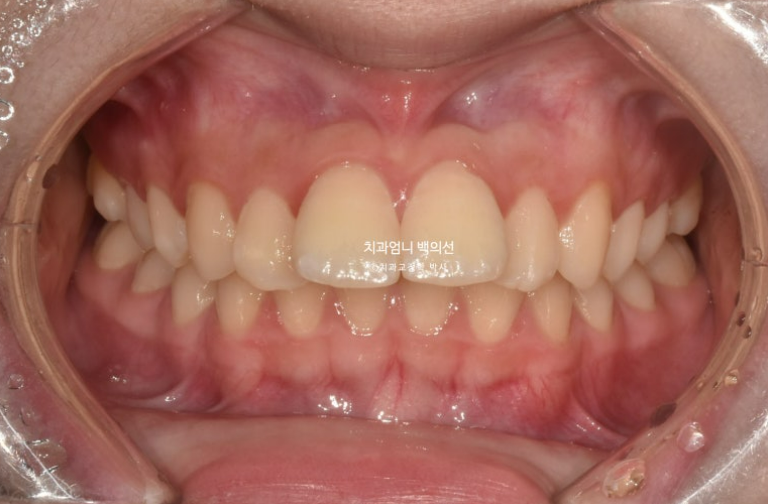

25.06

중심선은 잘 맞습니다.

유난히 커보이던 앞니는 돌출이 해소되고 가지런해지면서 누명을 벗었습니다.

교합은 좋습니다.

간혹 작은어금니 발치교정은 4개를 빼야 교합이 맞지 않나에 대한 질문을 듣는데 위에만 돌출인 경우 위에만 2개 빼는 교정도 좋은교합으로 마무리 되는 교정이랍니다.

그런데 파란화살표에 교정 중 양치가 잘 안되던 부분에 하얀 자국이 보이시죠. 브라켓이 붙어있던 네모모양을 제외한 주변이 초기충치로 얼룩덜룩 해진 모습입니다.

앞으로 관리가 잘 된다면야 큰 문제는 없겟지만 일부는 레진치료가 필요합니다.